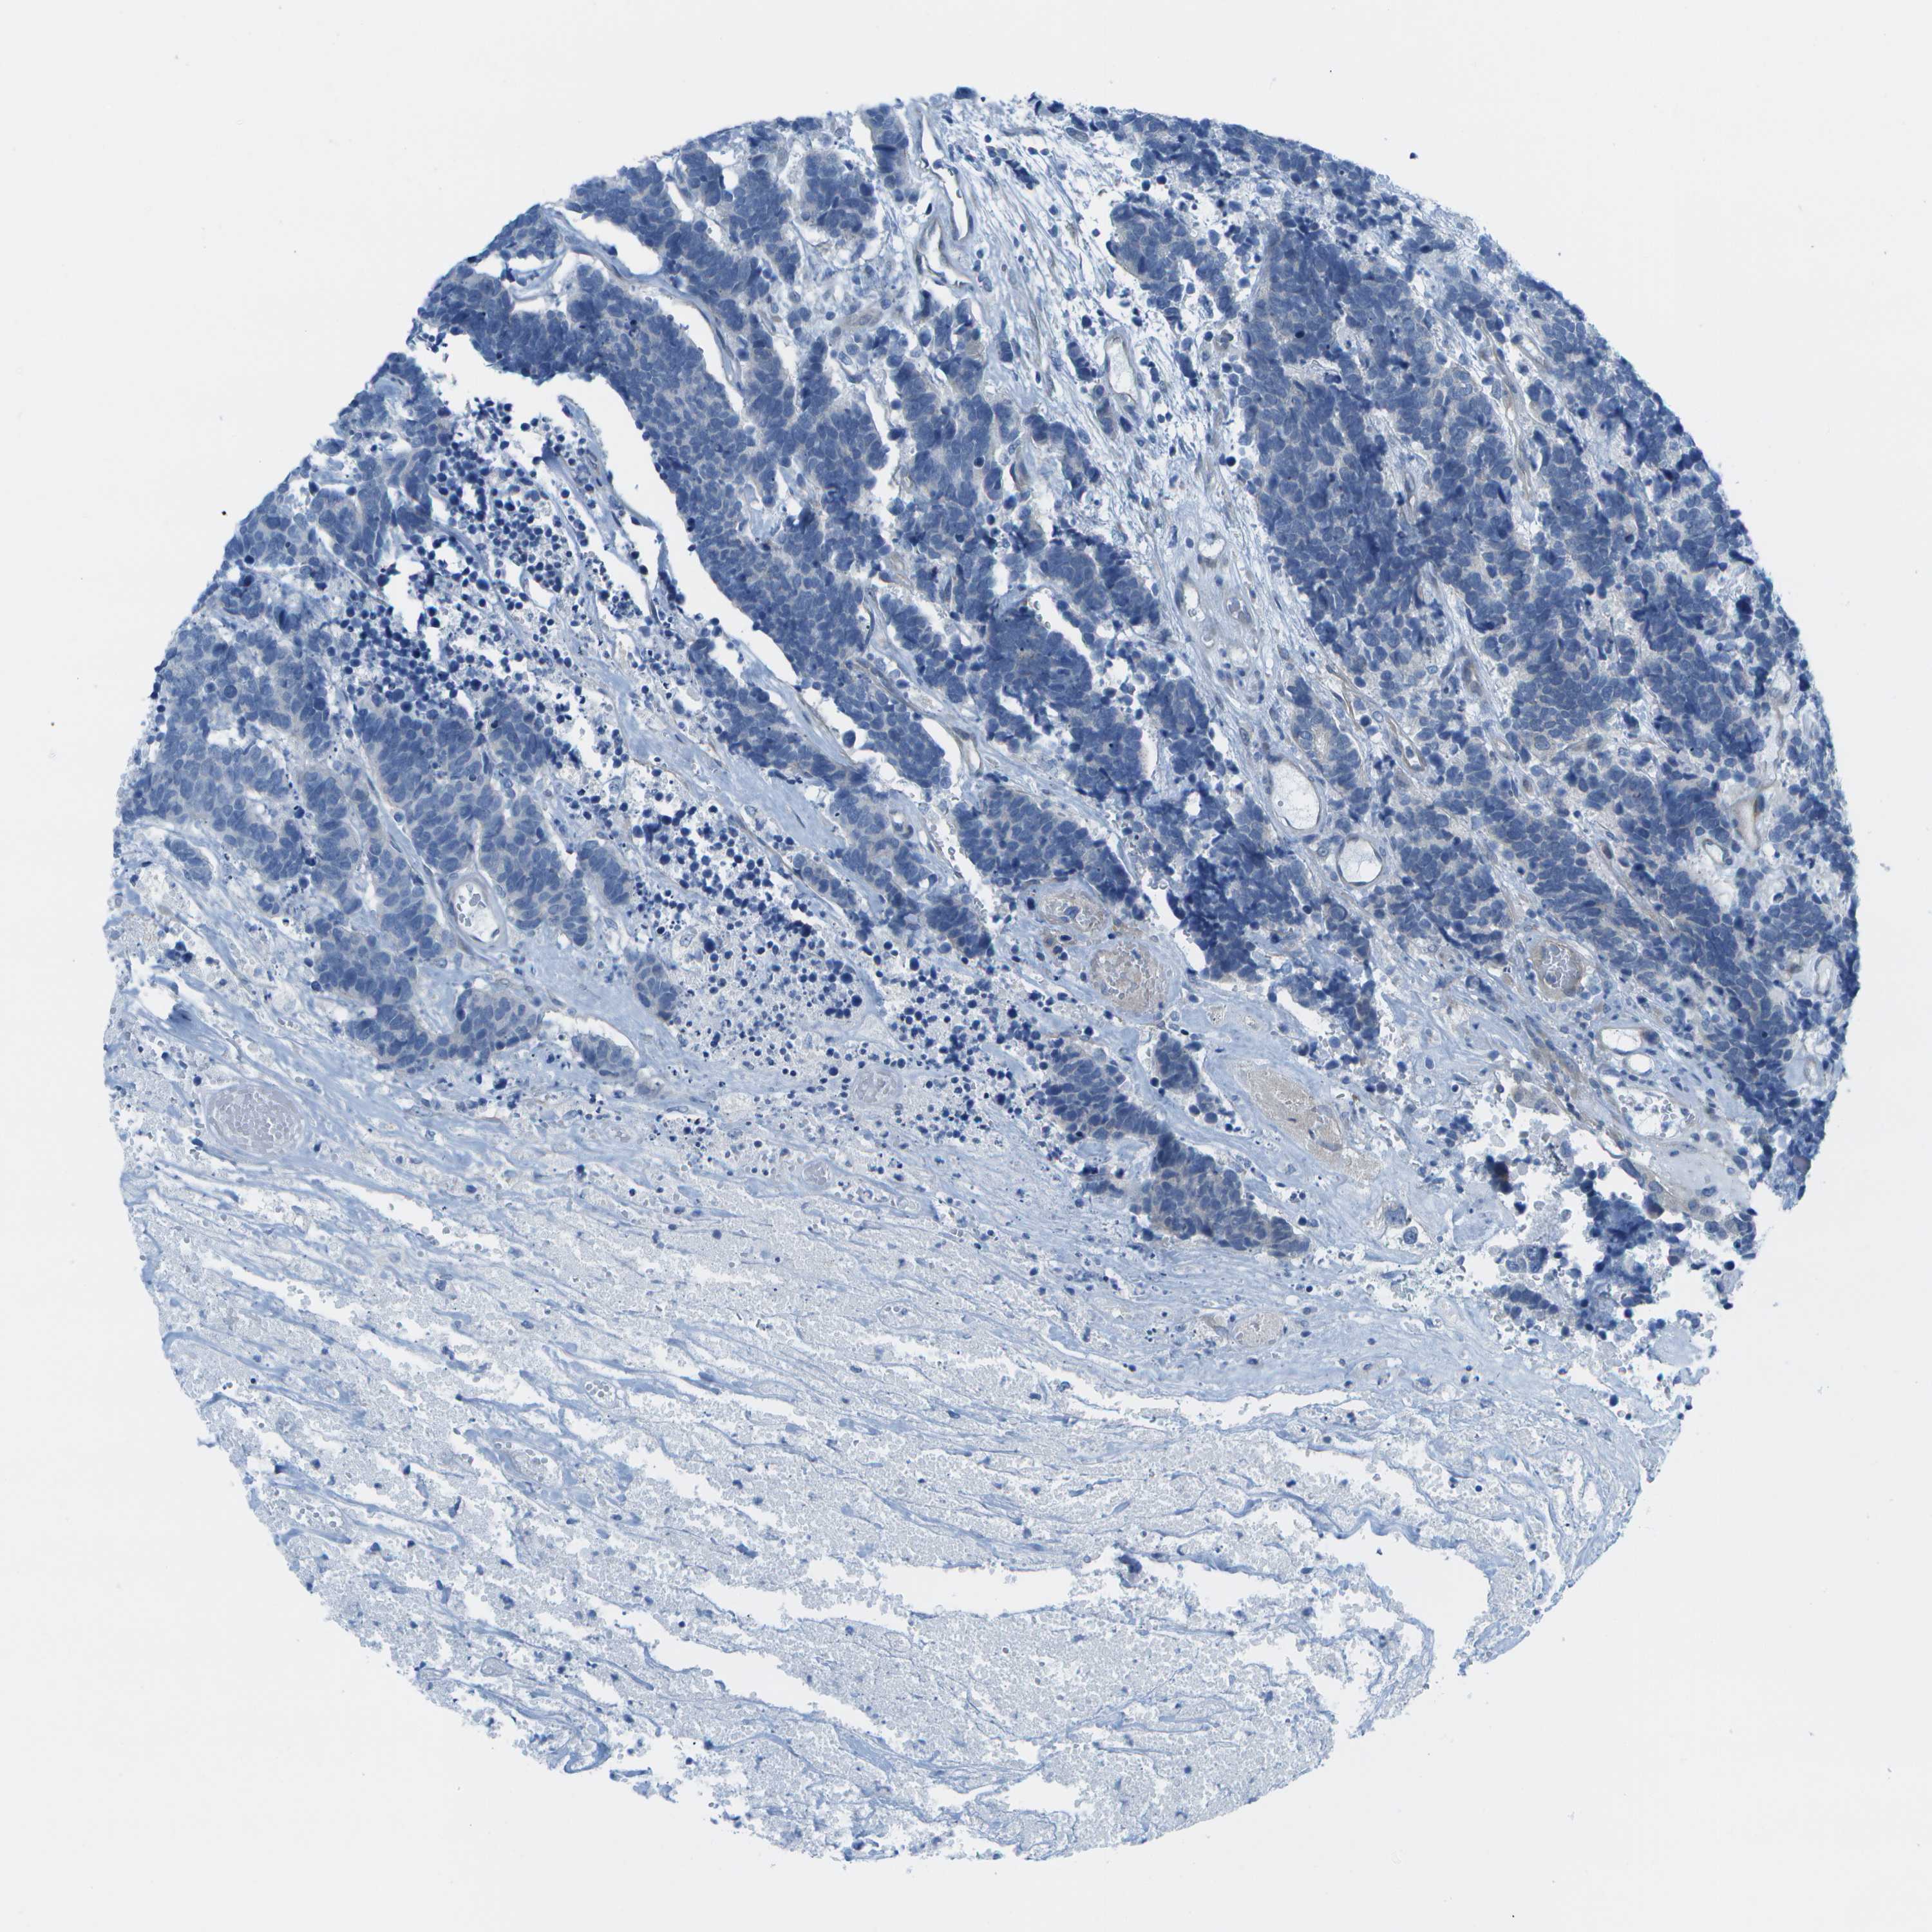

CARCINOID - Protein expressioni

A mouse-over function shows sample information and annotation data. Click on an image to view it in a full screen mode. Samples can be filtered based on level of antibody staining by selecting one or several of the following categories: high, medium, low and not detected. The assay and annotation is described here.

Antibody stainingi

Antibody staining in the annotated cell types in the current human tissue is reported as not detected, low, medium, or high, based on conventional immunohistochemistry profiling in selected tissues. This score is based on the combination of the staining intensity and fraction of stained cells.

Each image is clickable and will lead to virtual microscopy that enables deeper exploration of all samples and also displays staining intensity scores, fraction scores and subcellular localization as well as patient and tissue information for each sample.

Antibody HPA015849

Staining

High

Medium

Low

Not detected

Intensity

Strong

Moderate

Weak

Negative

Quantity

>75%

75%-25%

<25%

None

Location

Nuclear

Cytoplasmic/membranous

Cytoplasmic/membranous,nuclear

Carcinoid, malignant, NOS

Carcinoma, NOS